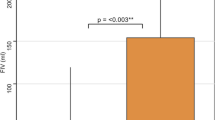

Descriptive statistics

Forty-four (51.6%) subjects had poor collaterals. Compared to patients with good collaterals, those with poor collaterals had worse NIHSS scores (median: 16.0, IQR: [12.8, 19.3] vs 13.0, IQR: [8.0, 18.0], p = 0.04), larger infarct cores (median: 43.7 mL, IQR: [28.0, 66.5] vs 9.5 mL, IQR: [5.0, 17.5], p < 0.0001) and higher increases in K2 (median: 346.3%, IQR: [64.9, 6955.5] vs 121.7%, IQR: [46.9, 201.7], p = 0.003) at admission. Figure 2 presents boxplots of increases in K2 expressed in a decimal logarithmic scale according to the status of cerebral collaterals. Patients with poor collaterals were less likely to achieve successful recanalization (21/44 vs 51/57, p = 0.004) and were more likely to experience hemorrhagic transformation (16/44 vs 9/57, p = 0.02). At follow-up, they had larger final infarct volumes (median: 48.9, IQR: [28.0, 71.3] vs 9.6, IQR: [5.0, 17.5], p < 0.0001) and poorer 3-month mRS (median: 2.0, IQR: [2.0, 3.0] vs 2.0, IQR: [1.0, 3.0], p = 0.004). The volume of the penumbra was not statistically different according to collateral status (p = 0.23). A very low correlation between penumbra volume and an increase in K2 was observed (Pearson coefficient = −0.19, p = 0.08).

Boxplot illustrating the increase in K2 based on cerebral collateral status. Patients with poor collaterals exhibited higher increases in K2 compared to those with good collaterals, although notable dispersion was observed. The thick black bar indicates the median and the box borders the first and third quartiles